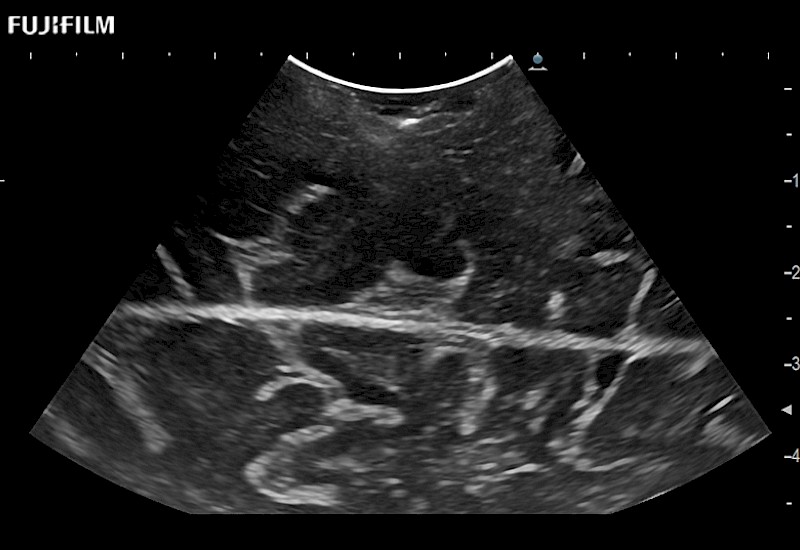

Tight curved (12mm) array transducer that is ideal for scanning during cranial guidance procedures.

Smaller footprint (20mm) curved array transducer that is ideal for scanning during cranial guidance procedures.

The ARIETTA 750 incorporates all of the proven technologies and functions that medical professionals have come to expect from Fujifilm Healthcare.

ARIETTA 750 is the definitive diagnostic ultrasound solution for any clinical setting - Private Office, Imaging Center, or Hospital. The ARIETTA platform provides the ultimate in clinical performance with its state-of-the-art features and large user-friendly display.

The ARIETTA 650 DI integrates the trusted technologies and features that neurosurgeons rely on from Fujifilm Healthcare.

ARIETTA 650 DI is the ideal guidance solution for the OR. The ARIETTA platform delivers exceptional clinical performance with advanced capabilities and a large, intuitive display designed for ease of use.

Learn moreFujifilm Healthcare continues to listen to the experts, our neurosurgeons, by developing an ultrasound system specifically designed for the Operating Room.

Guidance is the fundamental purpose for all of our surgical ultrasound technology. Fujifilm Healthcare is committed to designing tools that help neurosurgeons navigate inside the human body and provide the necessary information to immediately make critical surgical decisions.

With the ARIETTA Precision the next level of surgical ultrasound is here.